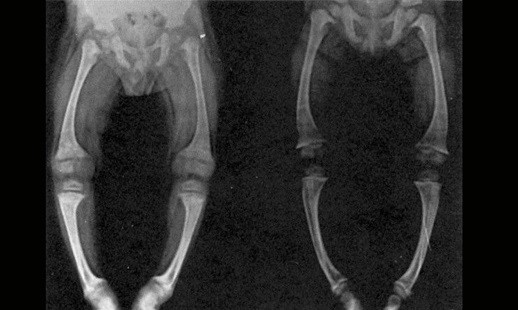

• Puede causar osteoporosis

es decir, disminución de la masa ósea y aumento de la fragilidad de los

huesos.

• Raquitismo:

baja mineralización y deformidad ósea, se da principalmente en los niños.